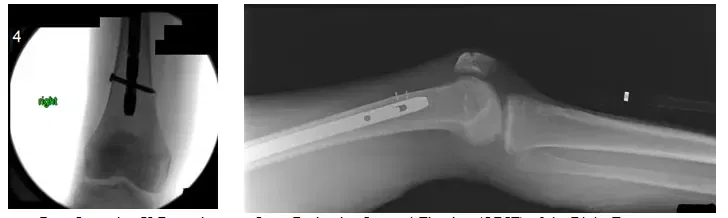

Les radiographies postopératoires montrent une fixation interne à réduction ouverte (ORIF) du fémur droit.

Les radiographies montrent une tige intramédullaire s’étendant du grand trochanter, à travers la fracture fémorale proximale, jusqu’à la tige distale du fémur où il y a une vis horizontale.

Lors du suivi, le patient a présenté un inconfort ou une douleur minimale, avait une bonne amplitude de mouvement à la hanche et au genou et porte un poids tel que toléré. Le patient a également reçu Forteo, qui est un agent osseux anabolisant qui augmente la formation osseuse. Le patient s’est bien porté par la suite.